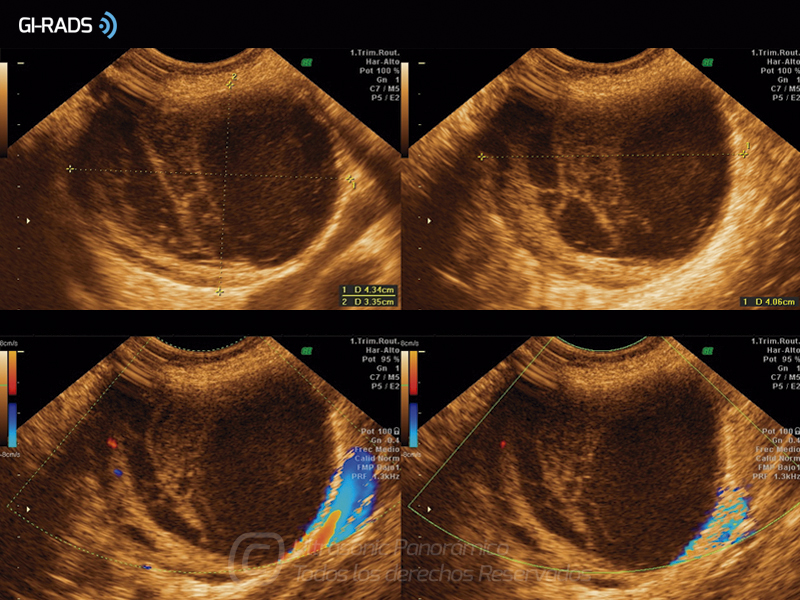

Patologías Benignas – Cuerpo Lúteo Hemorrágico

• Patologías Benignas – Cuerpo Lúteo Hemorrágico